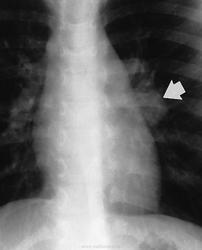

Различают инфильтративный, опухолевидный и малые формы туберкулеза внутригрудных лимфатических узлов. Опухолевидная форма проявляется увеличением размеров лимфатических узлов в результате воспалительной гиперплазии, что обнаруживается при рентгенологическом исследовании. Контуры лимфатических узлов на рентгенограмме и томограммах четкие. Инфильтративный туберкулез внутригрудных лимфатических узлов характеризуется не только увеличением узлов, но и развитием инфильтративных изменений в легочной ткани, в прикорневых ее отделах. Малые формы проявляются незначительным увеличением внутригрудных лимфатических узлов, что выявляется главным образом на томограммах с поперечным размазыванием в прямой или боковой проекциях. Этот вариант заболевания в последнее время встречается чаще, чем в прежние годы.

В современных условиях изменилась структура клинических форм туберкулеза, и появились нетипичные для повседневной практики его проявления. Повышенная восприимчивость к туберкулезу лиц, ранее не инфицированных микобактериями туберкулеза, способствует появлению туберкулеза внутригрудных лимфатических узлов (ТВЛУ) у взрослых. Неосложненное течение ТВЛУ у взрослых проявляется только рентгенологически односторонним или реже двусторонним увеличением различных групп внутригрудных лимфатических узлов. Неправильная оценка изменений во внутригрудных лимфатических узлах при туберкулезе ведет к распространению туберкулезного процесса на бронхи и легочную паренхиму. Возникают различной степени нарушения бронхиальной проходимости, которые сопровождаются развитием воспалительных изменений. Представляю наблюдение осложненного течения ТВЛУ у женщины 61 года, которая была направлена в РОНЦ с диагнозом: центральный рак правого легкого с ателектазом верхней доли. Рис. 1а, б. Верхняя доля правого легкого уменьшена в объеме, однородно уплотнена. Нижний контур доли вогнутый. Органы средостения в верхнем отделе умеренно смещены вправо. Диафрагма на стороне поражения расположена выше обычного. Рис. 2а, б, в, г. Компьютерные томограммы органов грудной клетки. На передней стенке правого главного бронха узелковые образования, перекрывающие частично просвет бронха. Верхнедолевой бронх нитевидно сужен. Верхняя доля правого легкого уменьшена в объеме, верхушечный и задний сегмент ателектазированы.

Неосложненное течение ТВЛУ у взрослых проявляется только рентгенологически односторонним или реже двусторонним увеличением различных групп внутригрудных лимфатических узлов.